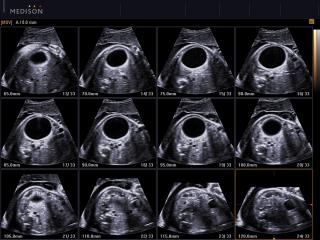

- MSV (Multi-Slice View или мультислайсинг) - возможность одновременного просмотра на экране множественных срезов, полученных при трехмерном сканировании.